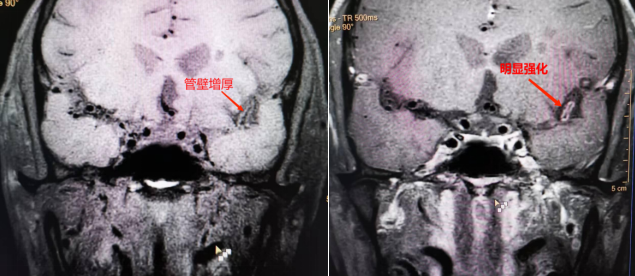

5招丨急性脑卒中取栓后复查

a55b33f997efcf18951086c6ba4e8a94.pngead81dee0f51b5b9d653166e1b441326.png

以上为急性脑卒中患者机械取栓后,HRVWI复查右侧大脑中动脉的图像,显示右侧大脑中动脉M1-3段管腔通畅,未见狭窄和血栓形成,取栓效果明显。